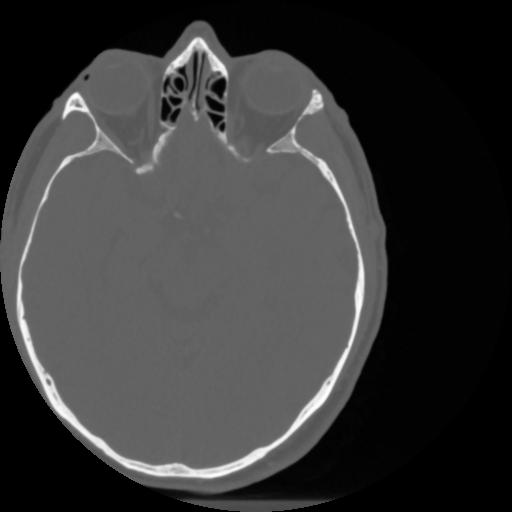

4 CEREBRO,,Vol,0.5,CEREBRO,,